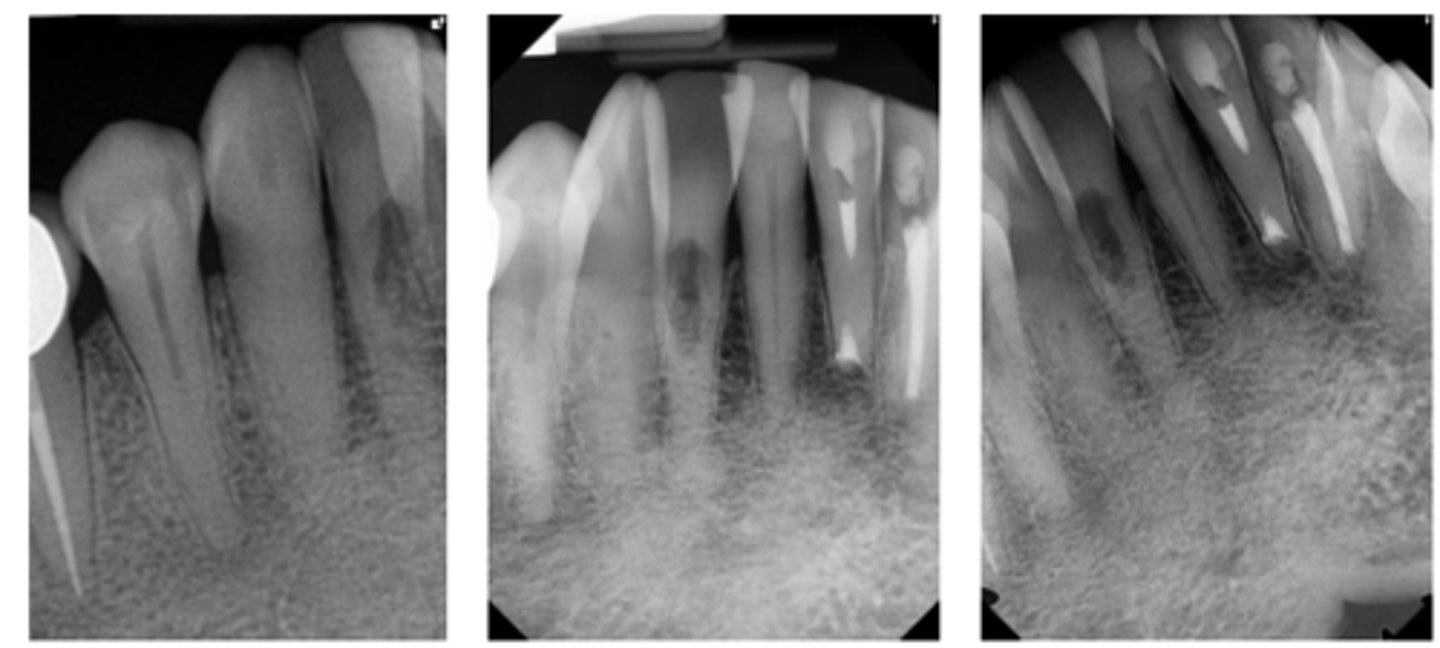

Internal inflammatory resorption

What is the diagnosis?

- Symmetrical ballooning of root canal

- Lesion does not move when PA is taken from different angles

- Usually does not have periapical lesion (Apical portion of root is vital!)

- Lesion may perforate into alveolar bone

- CBCT is recommended

Patient presents asymptomatic with a normal appearance but there is a pink/red spot on the tooth, what is the most likely diagnosis?

Patient presents with symmetrical ballooning of the root canal and lesion does not move when PA is taken from different angles. There is no PARL. What is the most likely diagnosis?